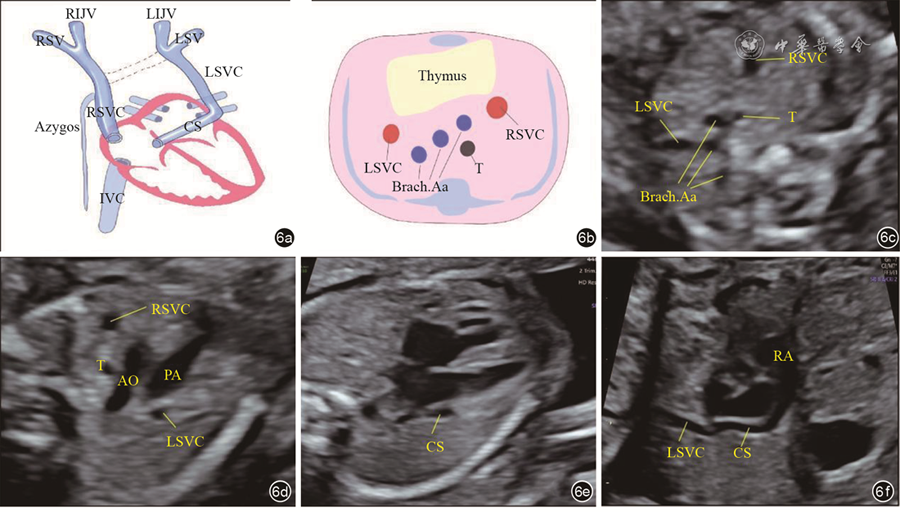

The 43 cases of LBCV abnormalities included the following three types: Abnormal course of the LBCV (traveling under the aortic arch in 25 fetuses, penetrating the thymus in 6, and retroesophageal or retrotracheal LBCV in 2); absent LBCV in 7 fetuses; and abnormal diameter of the LBCV (significantly widened inner diameter in 2 fetuses, and smaller inner diameter in 1). Nineteen were detected with other malformations, including right aortic arch, tetralogy of Fallot, transposition of the great arteries, persistent left superior vena cava, and total anomalous pulmonary vein communication. The mean inner diameter of the LBCV in normal fetuses at 18 to 34 weeks ranged from 1.9 mm to 3.98 mm, which showed a positive linear correlation with gestational age. The regression equation was: LBCV inner diameter (mm)=-0.6796+0.1352× gestational age (GA).

The position, course, and morphology of the LBCV can be observed by prenatal ultrasound. The inner diameter of the normal LBCV increases linearly with gestational age. Knowing the ultrasonographic features and clinical significance of different types of LBCV abnormalities can provide information and evidence for clinical consultation.